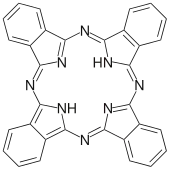

The mechanism of action for sonodynamic therapy is the use of low-intensity ultrasound through the use of focused mechanical waves to create a cytotoxic effect. However, SDT itself is non-thermal, non-toxic, and is able to non-invasively penetrate deep into tissue compared to other delivery methods such as photodynamic therapy. SDT is often performed alongside the use of a sonosensitizer such as porphyrin, phthalocyanines, xanthenes, and antitumor drugs.[17] Ultrasound waves are also classified as acoustic waves, and the effect they have on the tissue of application can be described by a process called cavitation. Cavitation occurs as a specific interaction between ultrasound and aqueous surroundings and causes gas bubbles to break upon exposure to particular ultrasonic parameters, thus promoting penetration of the therapeutic into the biological tissues by generating cavities near the edge of the membrane.[18][1] Cavitation can be broken down into stable and inertial cavitation. In stable cavitation, the oscillation of gas bubbles causes the environmental media to intermix.[1] In inertial cavitation, gas bubbles increase in volume and almost reach their resonance volume, swelling before aggressively collapsing.[1] The implosion of vesicles results in a drastic temperature and pressure change, thereby increasing the cell membrane's permeability to various drugs.[1][19] Microbubbles are created by the acoustic waves from the ultrasound that expand and collapse, releasing energy, bringing the sonosensitizer into an excited state, and generating a ROS. The cavitation of this gas bubble can form the ROS with different methodologies such as sonoluminescence and pyrolysis.[1] Apoptosis results from the formation of ROS and mechanical forces of SDT through membrane disruption in a process called lipid peroxidation. Necrosis is also a potential result of SDT.

Sonosensitizers

Sonosensitizers, or sonosensitizing therapeutics, are the primary element of SDT and can be tailored to treat various cancers and generate different effects.[2] These therapeutics, often involving the use of porphyrin or xanthene, will initiate a toxic effect via the ROS upon exposure to ultrasound.

| Phthalocyanine |  Phthalocyanine |